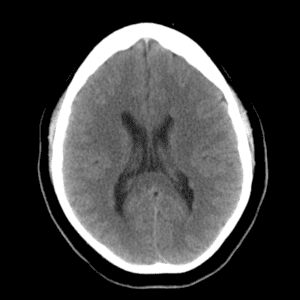

Case #10

Intraventricular meningioma